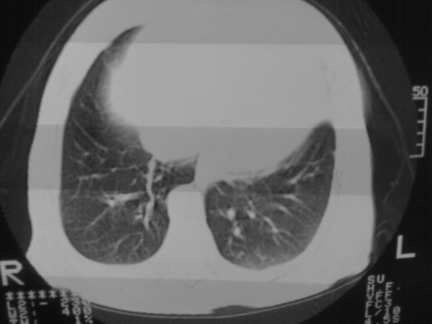

标题: CT13142:女 80 胸闷、气短、1w [打印本页]

标题: CT13142:女 80 胸闷、气短、1w

右肺炎性变,双侧甲状腺肿,胸膜肥厚。

右肺炎性变

双侧胸腔积液

缩窄性心包炎

左室为主的心脏增大。

胸膜肥厚,

气管,支气管软骨钙化。

右肺感染;双侧胸腔少量积液,心影增大,可能与心功不全有关;胸内甲状腺肿。

右肺炎性变,双侧甲状腺肿,胸膜肥厚,心影增大考虑心功能不全.

胸内甲状腺肿;右肺感染;双侧胸腔少量积液。

胸内甲状腺肿;右肺中叶感染;双侧胸腔少量积液;心影增大,考虑有心功能不全。